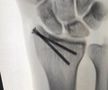

Calvarul prin care a trecut Lance Stroll pentru a lua startul în prima cursă de Formula 1 » Operat de urgență cu 12 zile înainte